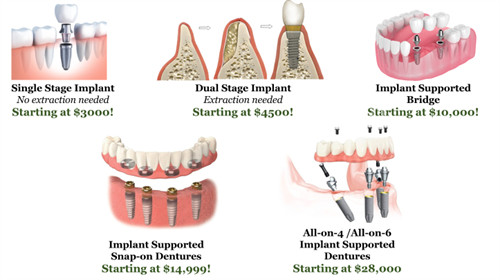

种植牙技术:苏医生擅长即刻种植、小创口种植及复杂骨增量手术,尤其对高龄缺牙患者的全口种植修复有独到经验。他主导的“即刻负重种植方案”可将传统种植周期缩短50%,实现“当天种牙当天用”。

“缺牙十几年,一直戴活动假牙,吃东西总不舒服。”65岁的张阿姨回忆道。经苏医生评估,她选择了“All-on-4”全口种植方案,仅植入4颗种植体即修复了半口咀嚼功能。“现在啃苹果、吃排骨都没问题,感觉年轻了20岁!”